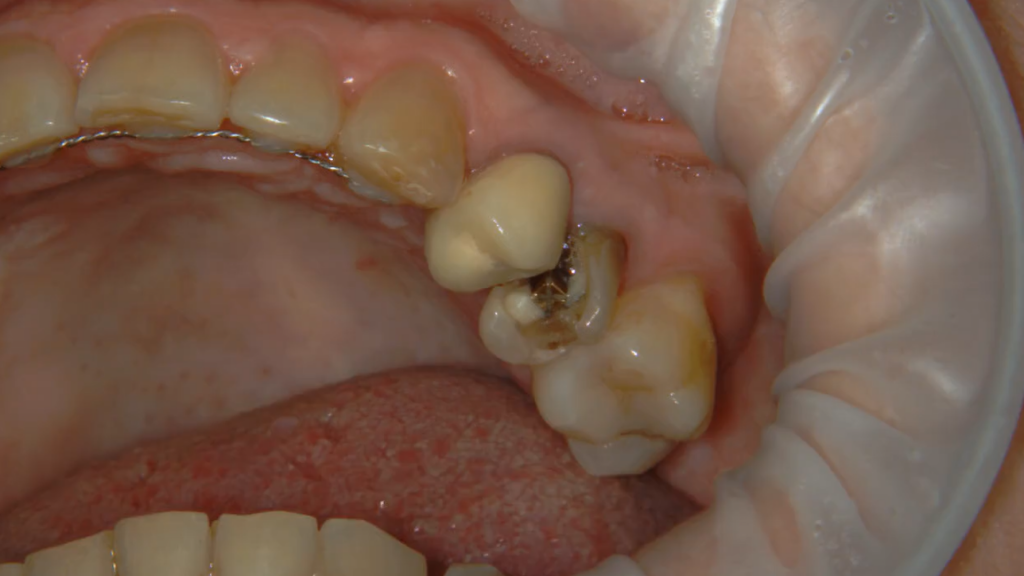

Описание клинического случая:

• Атравматичное удаление зуба 2.4, 2.5

• Одномоментная дентальная имплантация IMPRO

• Использование фибриновой мембраны Clot-PRF

• Установка временного абатмента IMPRO

• Изготовление индивидуального формирователя десны

Клинический случай Узденовой Зульфы Альбертовны